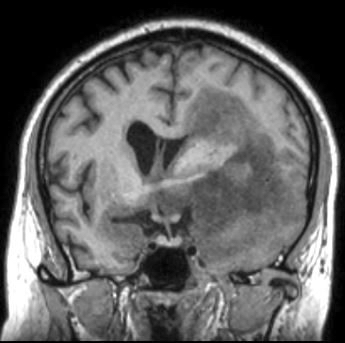

Radiology description

- CT:

- Expanding, intra-axial, poorly defined mass of low density

- Variable calcification may be seen

- Contrast enhancement and central hypodensity due to necrosis, occur with higher grades

- MRI:

- T1 hypodensity and T2 hyperintensity

- T2 hyperintensity with relative FLAIR sequence hypointensity (T2 FLAIR mismatch) is a relatively suggestive indication of IDH mutant astrocytoma (Clin Cancer Res 2017;23:6078)

- Distortion and enlargement of involved areas, including associated cortical ribbon

- Contrast enhancement is typically present in higher grade tumors (J Neurooncol 2019;141:327)

- Ring-like enhancement around central necrosis typical of grade 4

Radiology images